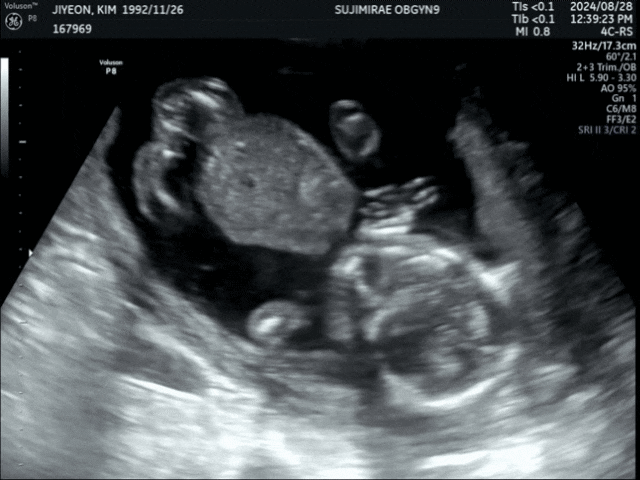

[8.28] 17주 3일차 임신중기 초음파 w/ 로링이?

17주 3일차?? 초코우유 따윈 필요없쥐.... 17주에도 아주 잘 움직이는 우리 로링잌ㅋㅋ 머리 요렇게 ...